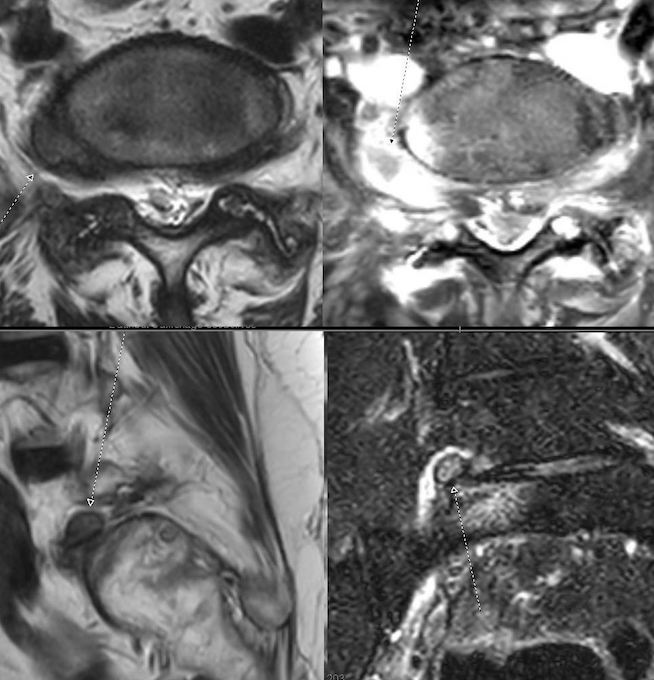

Musculosketal cases

Head and neck cases

Spine cases

Abdominal cases

Soft parts